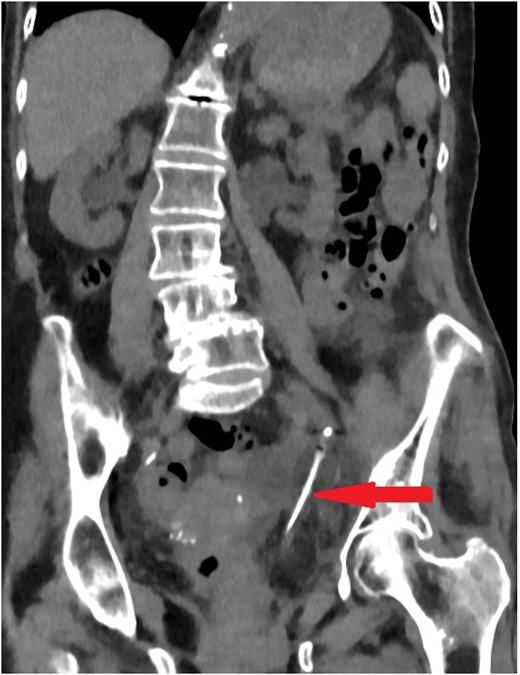

The old catheter was removed, and a replacement was inserted correctly into the bladder. The patient was managed conservatively with antibiotics. A further contrast CT was performed and showed mild extravasation of the contrast at the same level of the former catheter’s inflated balloon (Fig. 2). The patient improved clinically with conservative management, and her blood investigations remained stable. Follow-up contrast CT after 2 months was normal and showed no extravasation and no stricture (Fig. 3).

Coronal section of abdomen and pelvis contrast CT 24 h from the initial CT: The new urethral catheter balloon in the bladder (blue arrow). Contrast extravasates the left ureter at the site of the old catheter balloon (red arrow).